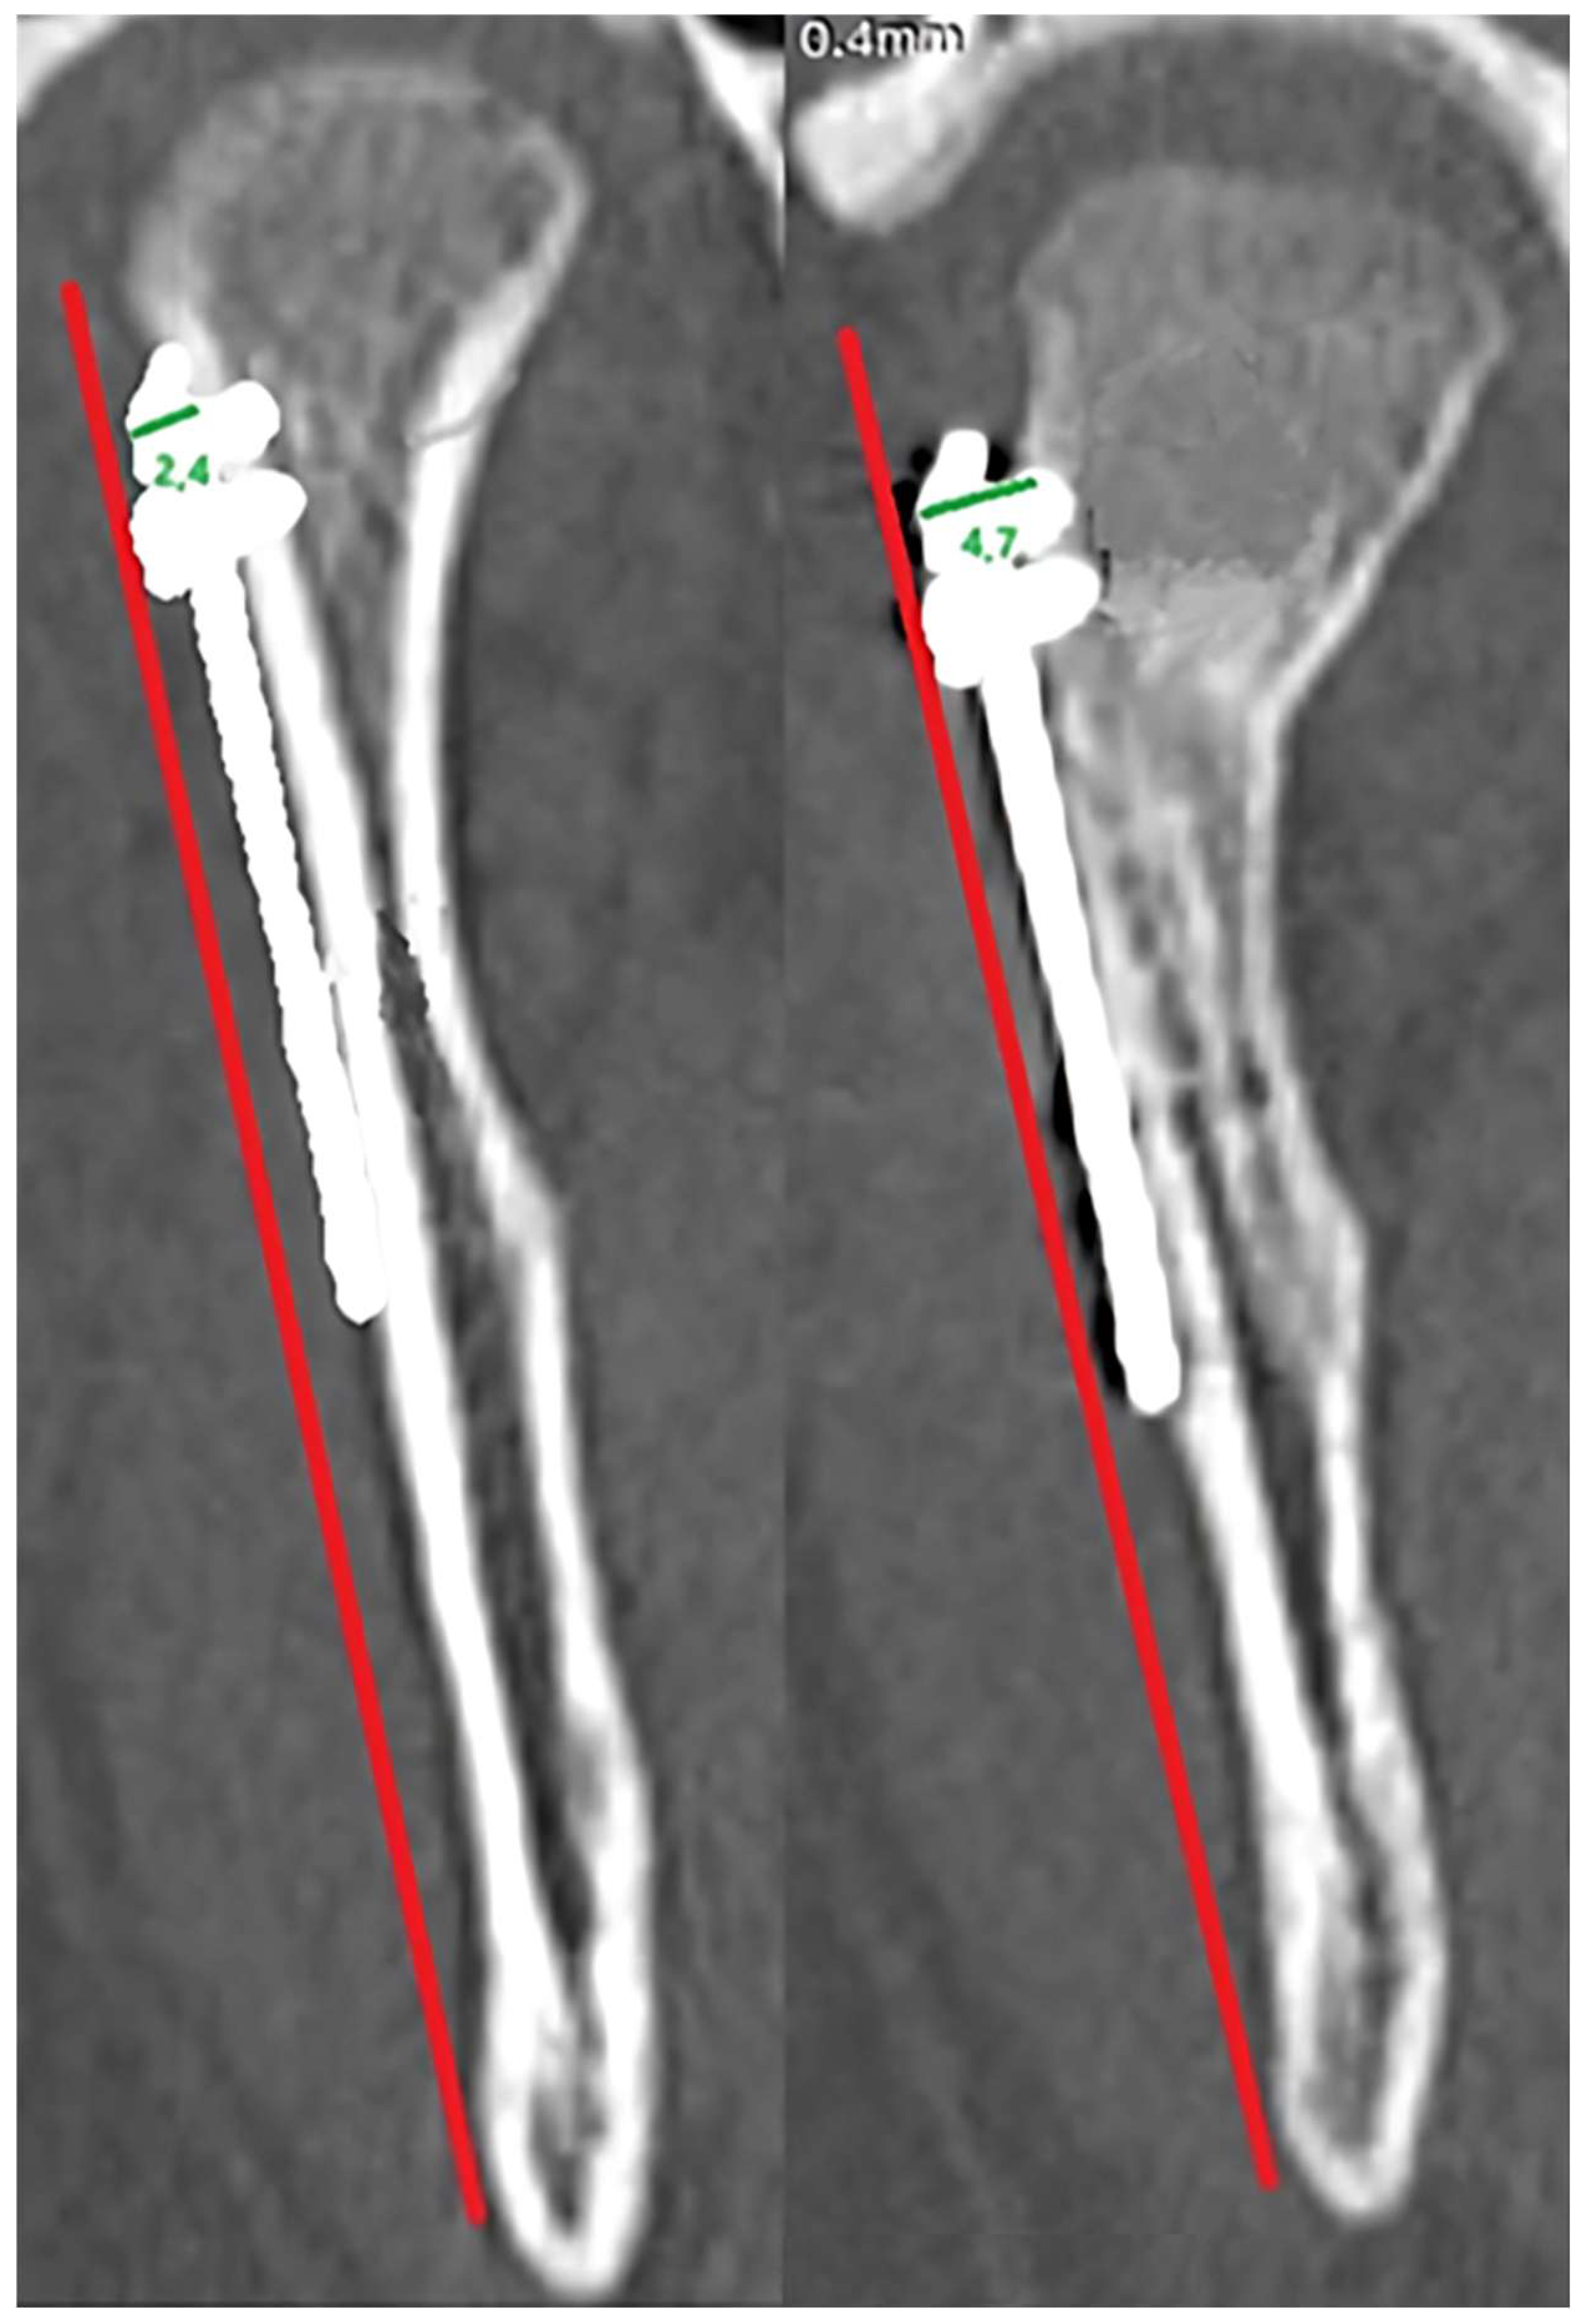

For each screw, the distance from the screw head to the bone border was measured parallel to the screw axis, immediately postoperatively and at 12-month follow-up. When resorption was observed around several screws, the mean value per plate was calculated. Measurements were taken in the frontal projection. A reference line perpendicular to the posterior border of the mandible was used to standardize orientation between scans.

The impact of the distance from the plate rim to the mandibular head lateral pole (in mm) is presented in

Figure 5. The values recorded ranged from those overlapping with the lateral pole (negative values) to a distance of as much as 20 mm. A statistical evaluation indicated that proximity to the lateral pole is a risk factor (

p < 0.05) for bone resorption at the plate rim (

Figure 5).

Osteosynthesis location was found to be related to resorption extent. Based on our findings, factors that induce resorption are not limited to plate insertion on the articular surface or covering the lateral pole of the mandibular head. Even lower osteosyntheses within the mandibular neck entail resorption. Only distant fixation, more than 14 mm away from the lateral pole, ensures no bone resorption at the osteosynthesis site. This finding is consistent with the biomechanical conclusions of Pavlychuk et al. [

Notably, the presented bone loss generally does not pose a threat to treatment outcomes, as it does not affect the loss mandibular ramus height. Exceptions here may include resorption observed at the upper rim of miniplates placed near the mandible head lateral pole. This may lead to involvement of the mandibular head in the resorptive process, shortening of the ramus and finally malocclusion. An exceptionally clinically devastating case may be seen in patients with significant bone resorption even on the lateral surface of the condylar process (away from the mandibular head), as this causes greater plate strain and may lead to plate fracture or pull-out of the fixation material due to exceeding the pull-out force for the residual screw fixation length (where the total length is usually only 6 mm). These results are in agreement with findings by Neff and Kolk [